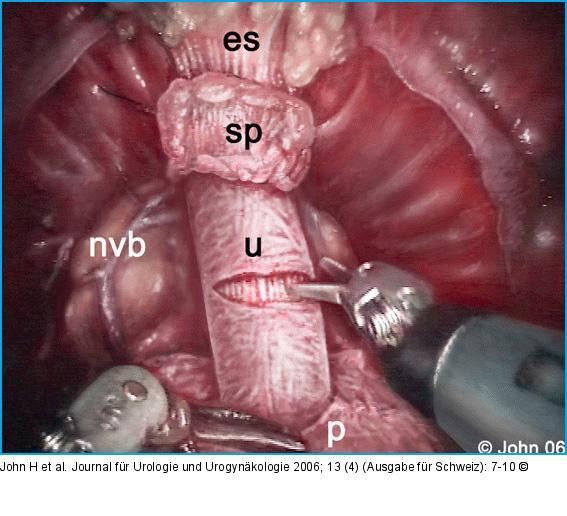

Abbildung 4a-i: DaVinci-Prostatektomie - Technik Die endopelvine Faszie wird beidseits inzidiert (a) und der Plexus Santorini aus Hämostasegründen durchstochen (b). Der Blasenhals wird schonend abgesetzt (c), die Adnexe abgesetzt (d) und die Prostata nach Eröffnen der Denovillierschen Faszie (e) vom Rektum abgeschoben. Die neurovaskulären Bündel werden nach Möglichkeit geschont (f). Apikal wird ein möglichst langer Harnröhrenstumpf gebildet (g) und das Präparat abgesetzt. Nach der vesiko-urethralen Anastomose (h) kann die Prostata über einen Endobag durch den infraumbilikalen Zugang geborgen werden (i). |

Die endopelvine Faszie wird beidseits inzidiert (a) und der Plexus Santorini aus Hämostasegründen durchstochen (b). Der Blasenhals wird schonend abgesetzt (c), die Adnexe abgesetzt (d) und die Prostata nach Eröffnen der Denovillierschen Faszie (e) vom Rektum abgeschoben. Die neurovaskulären Bündel werden nach Möglichkeit geschont (f). Apikal wird ein möglichst langer Harnröhrenstumpf gebildet (g) und das Präparat abgesetzt. Nach der vesiko-urethralen Anastomose (h) kann die Prostata über einen Endobag durch den infraumbilikalen Zugang geborgen werden (i). |